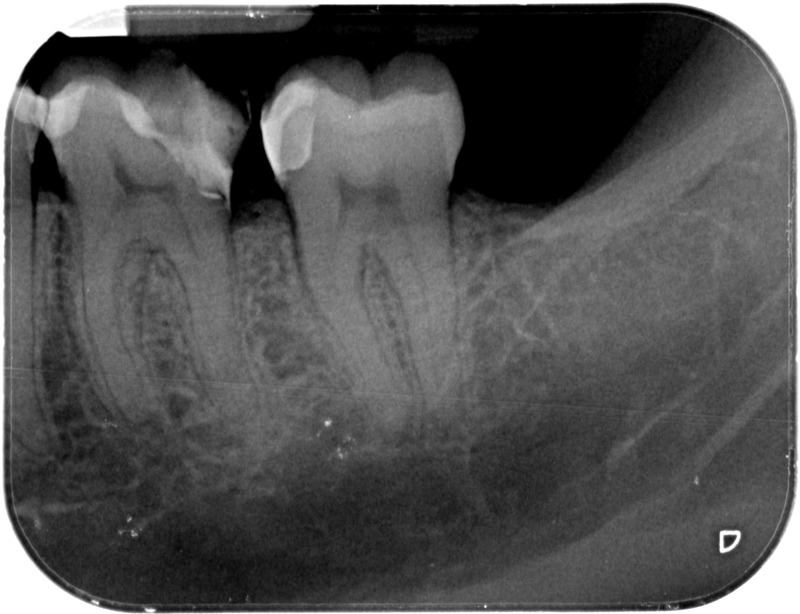

Après